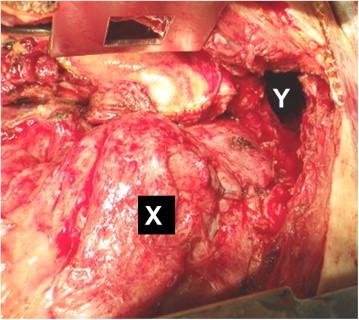

A 63-year-old man presented at our institution complaining of sudden left upper quadrant abdominal pain. Chest radiography showed a hyperdense lesion containing bowel gas in the left pleural space. Computed tomography revealed a dilated bowel above the diaphragm and intestinal obstruction suggestive of gangrenous changes. These findings were consistent with the diagnosis of incarcerated BDH and an emergency laparotomy was performed. Operative findings revealed the hypoplastic lung, lack of hernia sac, and location of the diaphragmatic defect, which indicated that his hernia was true congenital. Organs were reduced into the abdominal cavity, and large defect of the diaphragm was repaired with combination of direct vascular closure and intraperitoneal onlay mesh reinforcement using with expanded polytetrafluoroethylene (ePTFE) mesh. On the postoperative day 1, the patient fell into the shock and was diagnosed to have abdominal compartment syndrome (ACS). Conservative therapies were administered, but resulted in gastropleural fistula and pleural empyema, which required an emergency surgery. Mesh extraction and fistulectomy were performed.

一名63岁男性因突发左上腹疼痛就诊于我院。胸部X线检查显示左胸腔内有一个含肠气的高密度病变。计算机断层扫描显示膈肌上方肠管扩张及肠梗阻,提示有坏疽性改变。这些发现与绞窄性BDH的诊断相符,遂行急诊剖腹手术。手术发现肺发育不全、无疝囊及膈肌缺损位置,表明其疝为真正的先天性。将脏器还纳腹腔,用直接血管闭合联合使用膨体聚四氟乙烯(ePTFE)补片的腹膜内覆盖补片加强术修复膈肌大缺损。术后第1天,患者陷入休克,被诊断为腹腔间隔室综合征(ACS)。给予保守治疗,但导致胃胸膜瘘和胸膜脓胸,这需要急诊手术。进行了补片取出和瘘管切除术。